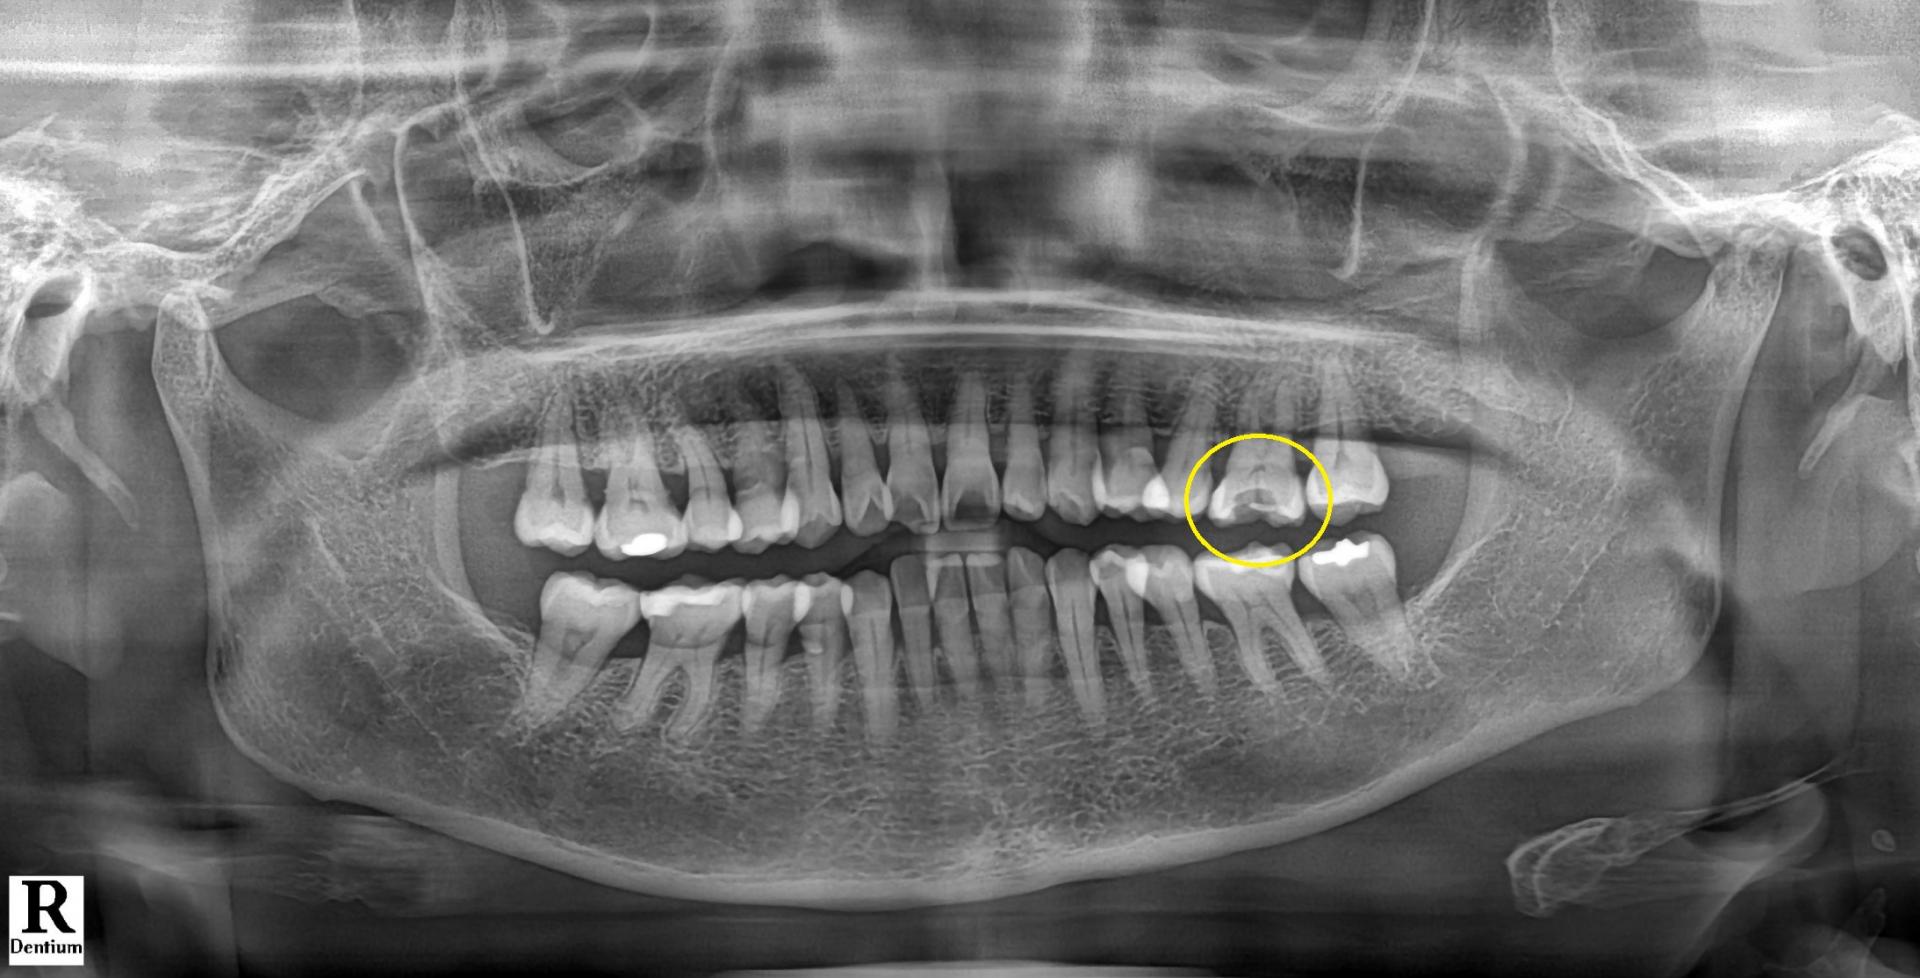

환자분의 구강 내를 직접 보기 전 x-ray 사진을 보면서 드는 생각은 통증이 없었다고 말씀하셨기에

"떨어진 부위 조금 다듬고 새로 보철물 만들어 드리면 되겠다."라는 간단한 접근이었습니다.